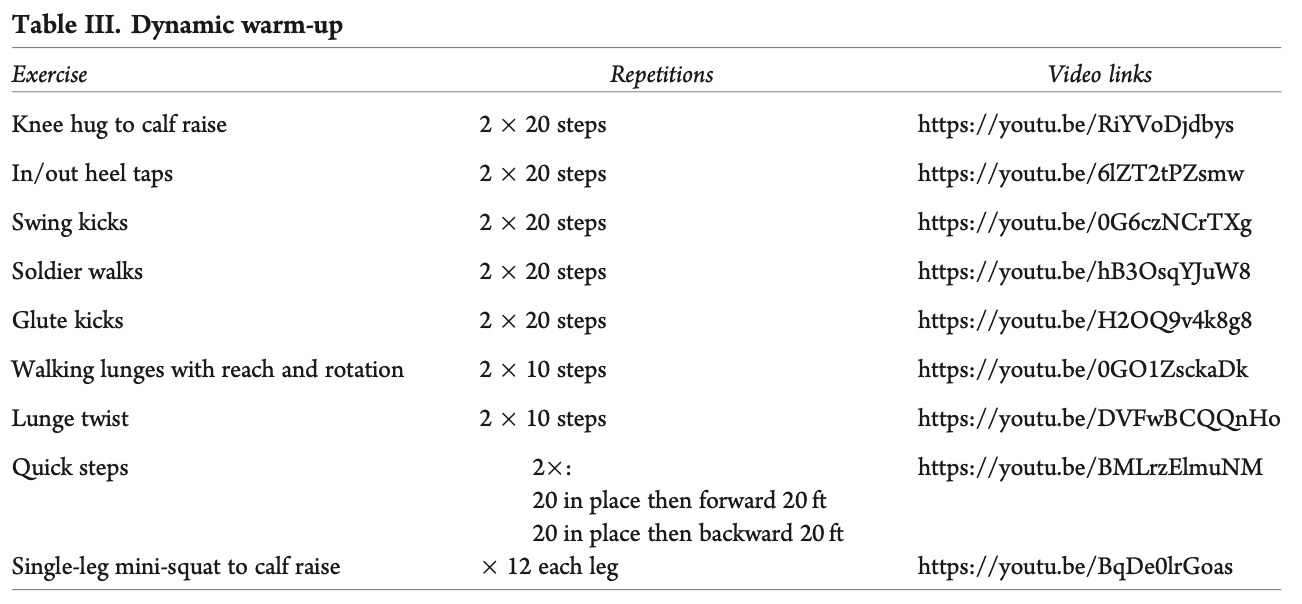

Преди всяка тренировка или бягане се изискваше динамична загрявка със следните упражнения. (А) прегръдка на коляното до повдигане на прасеца, (Б) потупвания с петата в/у петата, (В) ритници с люлка, (Г) войнишки походки, (Д) ритници в областта на седалището, (Е) ходещи напади с протягане и завъртане, (Ж) завъртане на напади, (З) бързи стъпки и (И) мини клек на един крак до повдигане на прасеца.